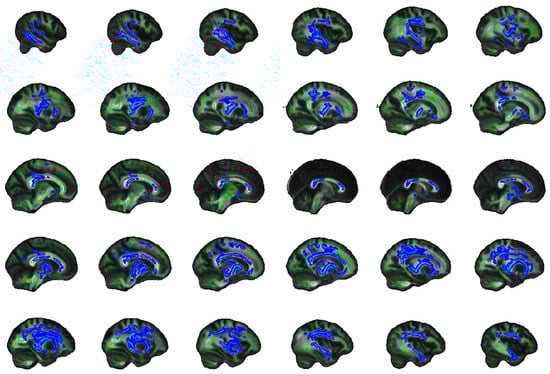

2.5. Exploratory Whole Brain Results

4.8. Exploratory Whole Brain Analysis

| Tracts | Side | Peak Voxel (MNI) | F-Statistic (TFCE) | Cluster Size > 100 (Voxels) | Cluster p-Value | ||

|---|---|---|---|---|---|---|---|

| x | y | z | |||||

| FA | |||||||

| SFOF | Left | −22 | −2 | 19 | 19.5 | 10,610 | 0.001 |

| ILF | Right | 45 | −11 | −27 | 14.2 | 6452 | 0.003 |

| UNC, IFOF | Right | 18 | 24 | −12 | 13.8 | 669 | 0.015 |

| AD | |||||||

| Unclassified | Left | −10 | −1 | −14 | 17.3 | 12,958 | 0.001 |

| ILF | Right | 40 | −22 | −21 | 11.5 | 1739 | 0.014 |

| Forceps minor | Right | 12 | 31 | 8 | 10 | 1522 | 0.028 |

| UNC, IFOF | Right | 28 | 14 | −10 | 9.84 | 786 | 0.03 |

| Unclassified | Right | 1 | 10 | 14 | 7.64 | 188 | 0.047 |

| Forceps minor | Left | −12 | 29 | −12 | 9.1 | 157 | 0.042 |

| SLF | Left | −34 | −37 | 21 | 10.3 | 141 | 0.038 |

| ATR, IFOF | Right | 23 | 26 | 23 | 5.94 | 141 | 0.047 |

| MD | |||||||

| ATR | Left | −11 | −17 | −2 | 18.1 | 31,113 | 0.001 |

| RD | |||||||

| ATR | Left | −23 | −2 | 17 | 18.8 | 14,709 | 0.001 |

| ILF | Right | 45 | −10 | −28 | 15.3 | 6641 | 0.004 |

| UNC, IFOF | Right | 18 | 24 | −12 | 13.4 | 209 | 0.039 |